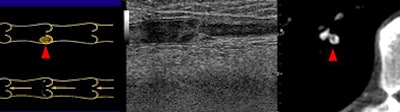

| Above, small peripheral pulmonary emboli are common and are of unknown clinical importance. Image below shows a patient with classic pulmonary embolism, with larger clots involving the central pulmonary vasculature and deep vein thrombosis. All images courtesy of Jane Suh and Dr. John Cronan. |

The retrospective study examined the medical records of 1,273 consecutive patients, of whom 101 (7.9%) were diagnosed with pulmonary embolism at CT. The researchers further evaluated 50 patients (24 men, 26 women; ages 21-90 years; mean age, 56.1 years) who also underwent lower-extremity venous ultrasound performed within seven days of the CT.

"We reviewed all images and plotted the clots on a diagram of pulmonary vasculature, and also measured the width of the most proximal clot for each patient," Suh explained.

In 32 patients (64%), extensive clotting was noted in the central pulmonary arteries (divisions 1-3), constituting classic PE, she said. In 18 of these cases (56%), deep vein thrombosis (DVT) was also diagnosed with ultrasound.

But in the 18 remaining cases diagnosed with pulmonary emboli, the researchers found only tiny clots in the fourth- through sixth-generation pulmonary arteries ranging in size from 1.5 mm to 4 mm (mean, 2.3 mm). In all, 27.7% of PE cases (28 of 101) at their institution were "dots," with an average width of 2.5 mm, she said.